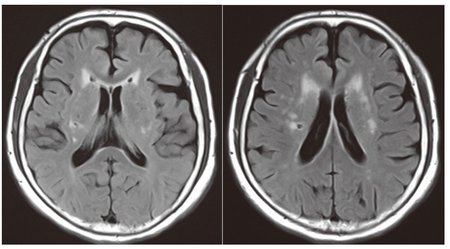

多発性硬化症は、脳の白質と灰白質の両方に影響を与える可能性があります。これにより、疲労や記憶喪失などの神経症状が引き起こされる可能性があります。

多発性硬化症 (MS) は、脳や脊髄を含む中枢神経系の慢性疾患です。 MSが脳の白質に影響を与えることは専門家らの間で長年知られていたが、2017年に発表された研究では灰白質にも影響を与えることが示唆されている。

MS は脳の白質と灰白質に損傷を与える可能性があります。時間が経つと、身体的および認知的症状が生じる可能性がありますが、早期に治療すれば効果が得られる可能性があります。